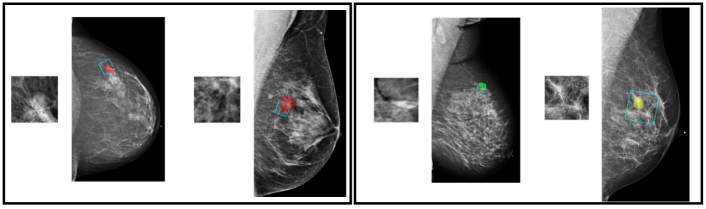

This DCNN is used to produce representations of local information. It is denoted as and is shown in Figure 4a. We use DenseNet-161 [31] as its architecture. We add an additional fully-connected layer with 32 neurons between the global average pooling layer and the classification layer to obtain concise representations of the patch. The additional layer results in the feature vector for the patch, which we use as the representation for the local information extracted by .

To further incorporate global image context and curate the local information extracted by the DCNN, we train an “aggregation network” with inputs formed by aggregating maps containing information relative to the patch and the image it is cropped from, as illustrated in Figure 4b. This aggregation network is a shallow convolutional network, denoted as . It consists of two convolutional layers, each with 32 convolutional filters, a global average pooling layer and, finally, a classification layer. We apply batch normalization and the ReLU activation function prior to each convolutional layer. This network is trained for the same patch classification task. The maps formed as inputs to the aggregation network are described in the following paragraphs.

![]() |

During training, we consider patches from mammograms with and without lesions, and perform multi-class classification over four classes: malignant, benign, outside and negative. In the validation and test phases, we only consider patches from images with lesions, and transform the patch-level predictions into a malignancy prediction for each lesion in the images. To get a prediction for a lesion, as shown in Figure 5, we crop 100 patches that overlap with the segmentation of the lesion. The size of the cropping window varies from 128128 to 384384 pixels, which is the same range we used for data augmentation. After cropping, each patch is resized to 256256 pixels, and we use it as input to to produce a feature vector. Then, we apply on the concatenated maps, including the embedding maps transformed by the feature vector and we get its prediction, each as four scores for the four patch classes. For each patch, we normalize the scores for malignant and benign patch classes so that they sum to one. Finally, we average the 100 normalized scores of the 100 sampled patches to obtain a prediction for the lesion. Based on these estimated probabilities, we compute the AUC that the model achieves in classifying the lesions as malignant or benign. We use the AUC computed on the 850 lesions from the validation set for model selection, and report the AUC computed for the 600 lesions from the test set.